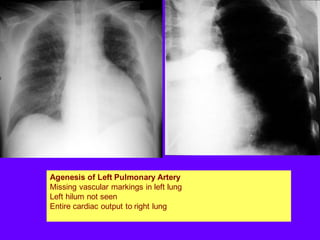

Agenesis of Left Pulmonary Artery

Missing vascular markings in left lung

Left hilum not seen

Entire cardiac output to right lung